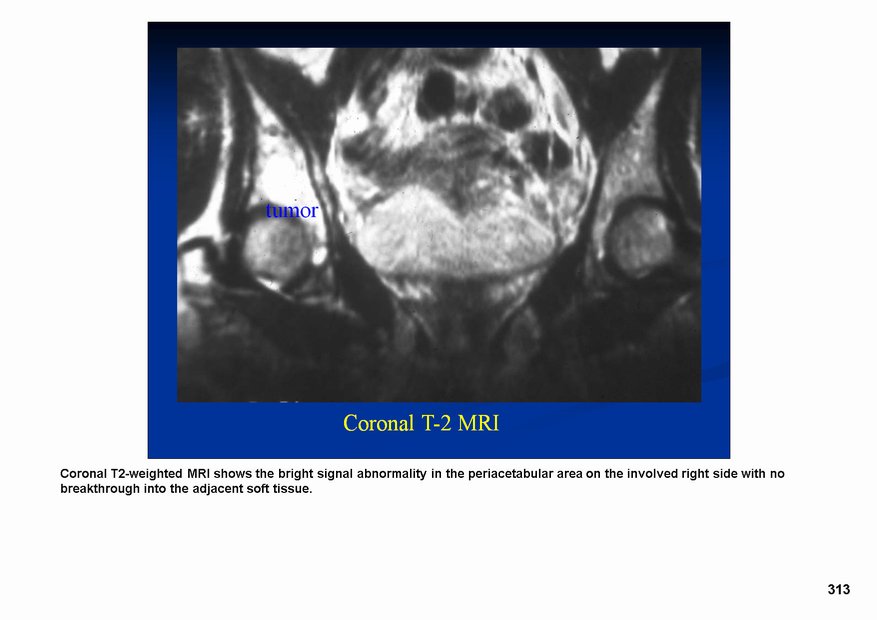

Дедифференцированная хондросаркома